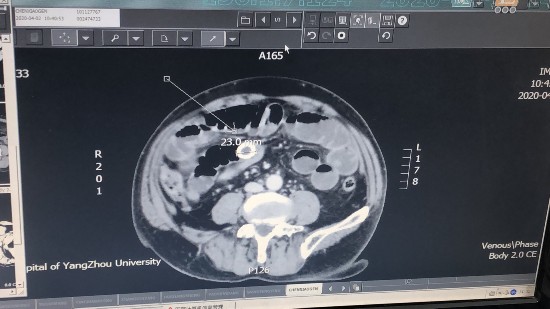

经检查发现,陈师傅小肠里有一直径约2.3厘米的环形异物。陈师傅纳闷,他并没有吞下任何异物,怀疑是吃东西时将碎牙咽进了肚子里。医生建议通过手术把这个异物取出来。

扬大附院胃肠外科主治医生汤晓飞介绍,经过手术发现,陈师傅腹部的疼痛是胆囊结石引起,结石穿孔游走到小肠内造成肠梗阻。